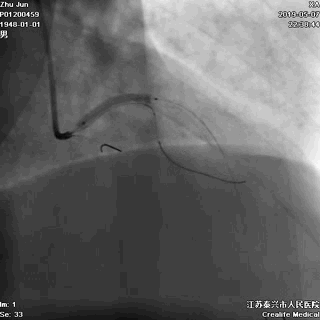

一、指引导管到位

---防止导管嵌顿和深插

主干开口病变,指引导管嵌顿或深插,就可能一招致命

游离一根导丝至升主动脉,防止导管深插

轻轻冒烟,证实指引导管到位

轻轻冒烟,大致了解前降支的情况

这一步相当重要。否则,无论是导管嵌顿,还是导管深插,稍不留意患者都有可能一招致命。